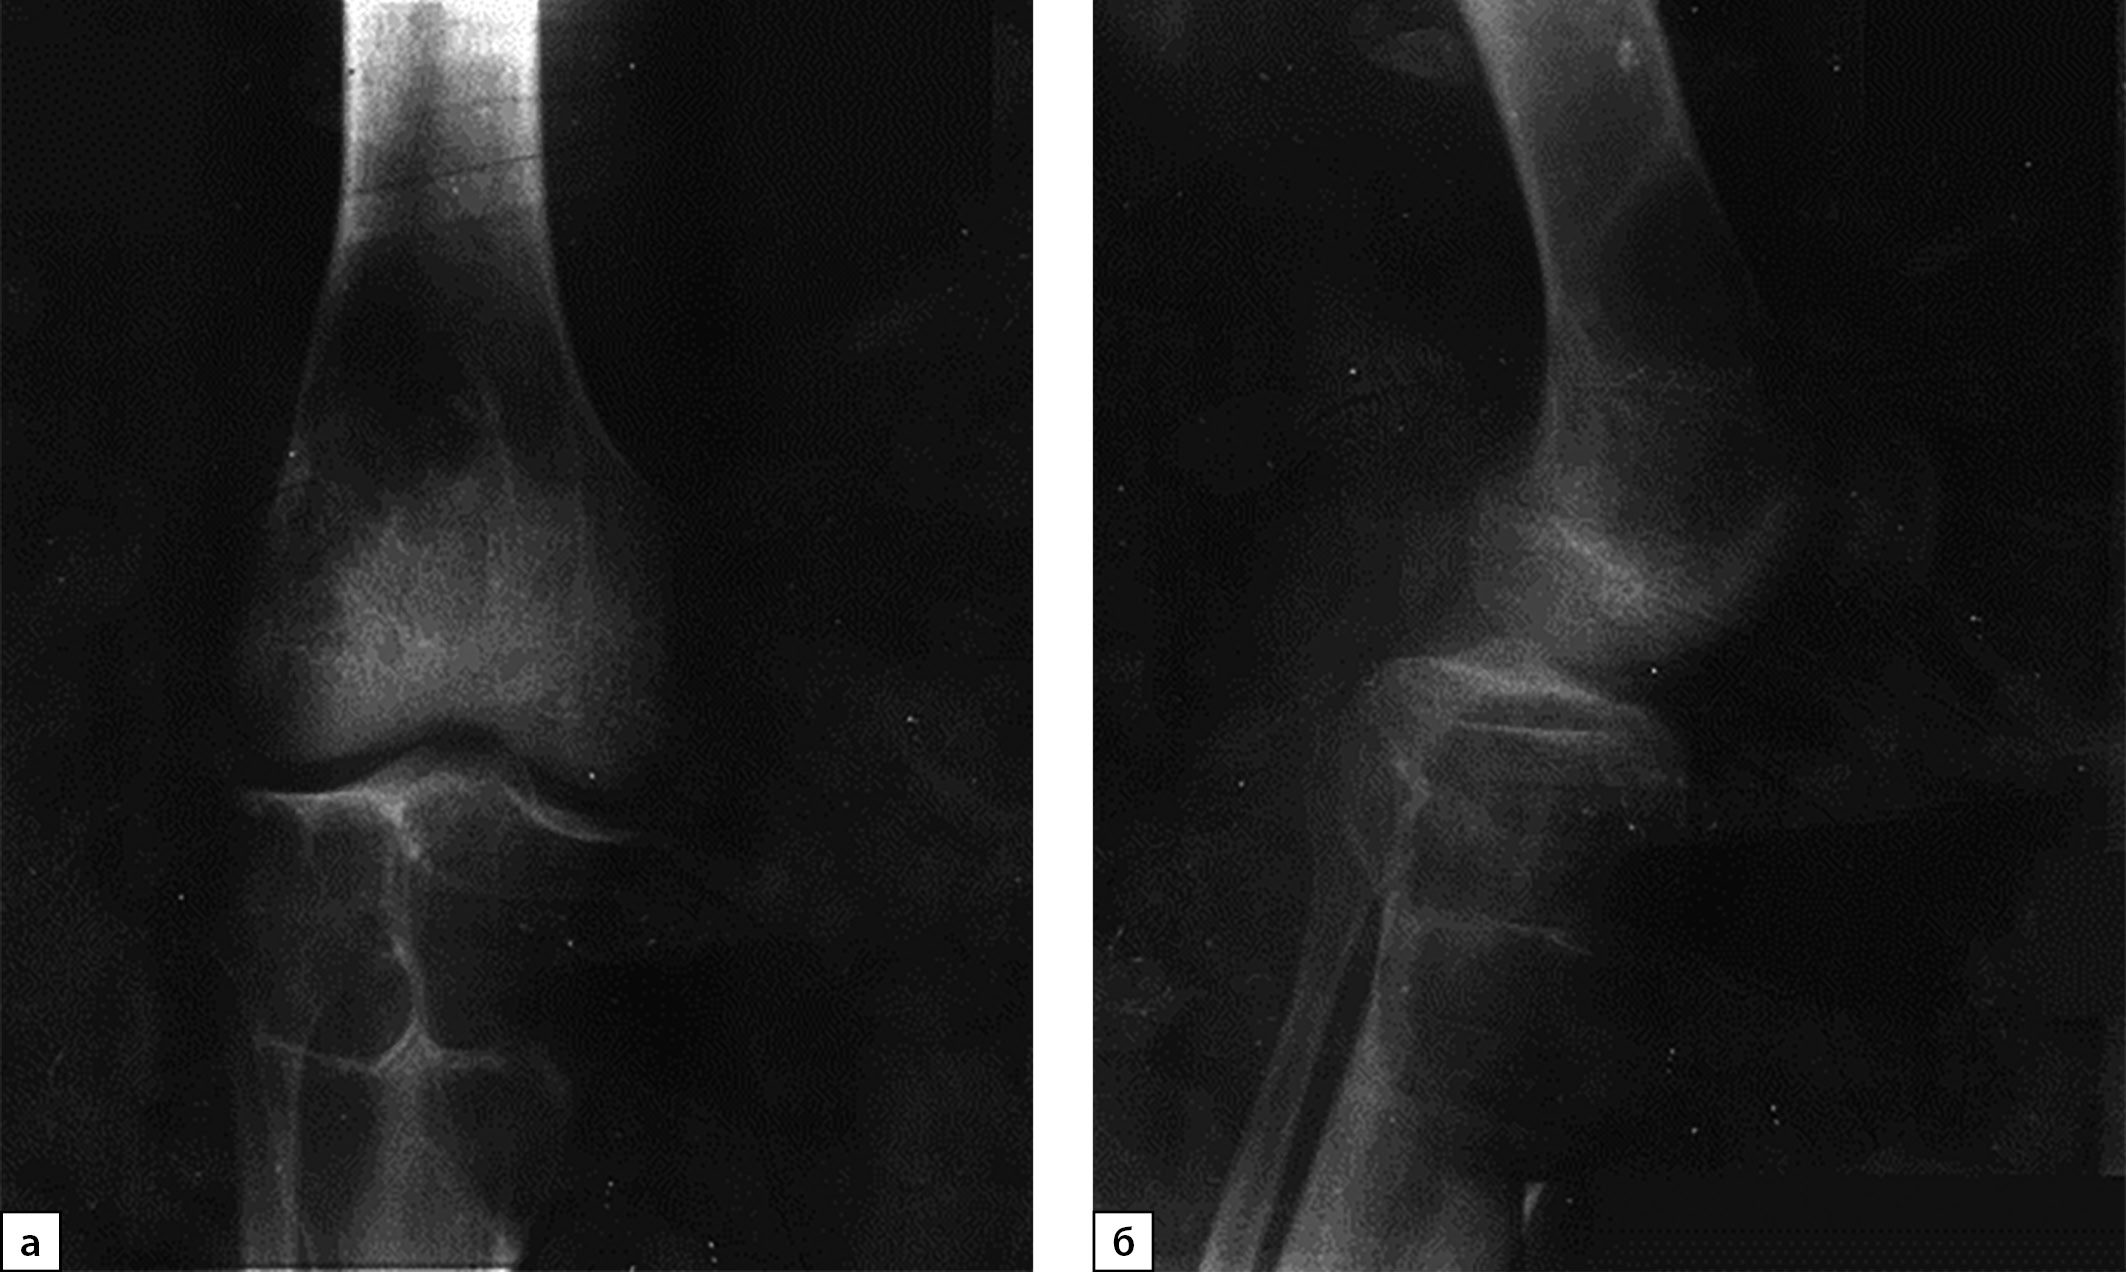

В июле 2020 г. после низкоэнергетической травмы (падения) при рентгенологическом исследовании правого коленного сустава выявлены множественные очаги деструкции костей, образующих коленный сустав. Данные изменения расценены как множественные кисты (рис. 1, а, б). По данным магнитно-резонансной томографии (МРТ) также подтверждены признаки множественных кист в дистальных метаэпифизах бедренных и проксимальных отделах большеберцовых костей с обеих сторон, справа — с разрушением кортикального слоя кости (рис. 2, а, б).

Рисунок 1. Рентгенография правого коленного сустава с литическими очагами бедренной и большеберцовой костей, 2020 г. (в прямой (а) и боковой проекциях (б)).